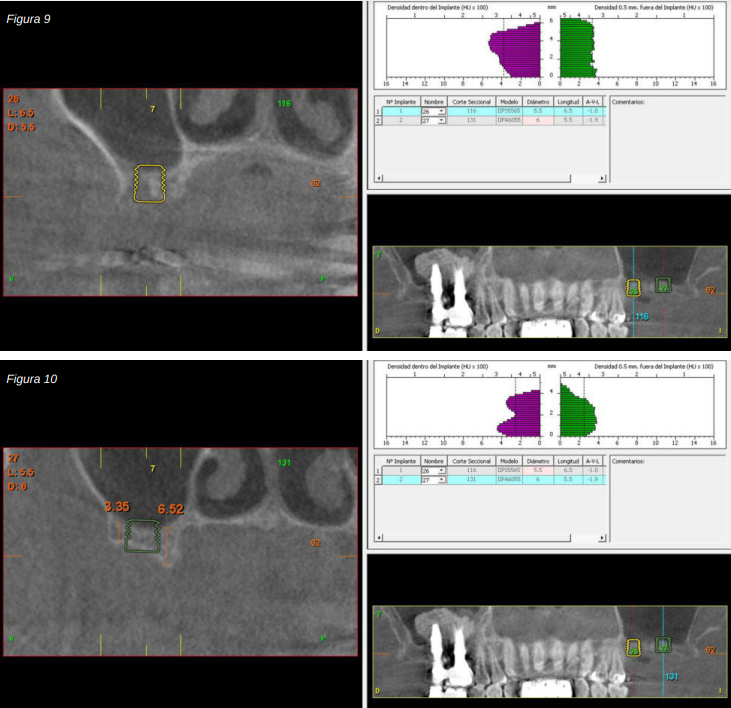

Transcurridos cuatro años, los molares del segundo y tercer cuadrante comienzan a tener una movilidad excesiva y problemas periodontales graves, por lo que se decide la extracción de los mismos y la regeneración de los alveolos con PRGF-Endoret. Una vez regenerada la zona (mes y medio después) se procede a la obtención de un Cone-beam para evaluar el volumen óseo residual. En el mismo se puede observar cómo existe una cresta ósea desigual con zonas de 3,3 mm de altura hasta 7 mm como máximo (Figuras 9 y 10). En esta ocasión, debido al cambio de protocolo descrito anteriormente, se opta por la inserción de implantes extra-cortos de forma directa, ya que los protocolos quirúrgicos para abordar este tipo de situaciones en el año 2011 variaron sustancialmente, siendo estos implantes una herramienta de primera línea para el tratamiento de este tipo de atrofias (Figura 11). Se seleccionan dos implantes extra-cortos (5,5 mm de diámetro x 6,5 mm de longitud para la pieza dental número 26 y 6 mm de diámetro por 5,5 mm de longitud para la pieza dental número 27).